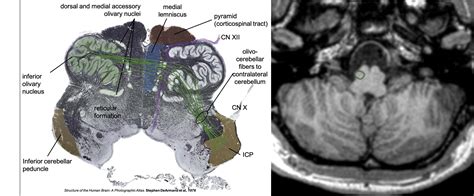

The Superior Olivary Nucleus is situated in the pons, a part of the brainstem. It is composed of several subnuclei, each with distinct functions and connections. The primary subnuclei include the medial superior olive (MSO) and the lateral superior olive (LSO). The MSO is particularly important for processing ITDs, which are differences in the arrival time of sounds between the two ears. The LSO, on the other hand, is crucial for processing ILDs, which are differences in sound intensity between the two ears.

The SON receives inputs from both ears through the cochlear nuclei, which are the first relay stations in the auditory pathway. These inputs are then integrated and processed within the SON to extract spatial information about sound sources. The processed information is subsequently sent to higher auditory centers, such as the inferior colliculus and the auditory cortex, where it is further analyzed and integrated with other sensory information.